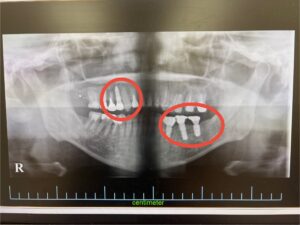

右上に1本、左下に2本の計3本のインプラントを同日に埋入する治療計画としました。(元々右上に1本、左下に1本の計2本はインプラントされてました。)

術後